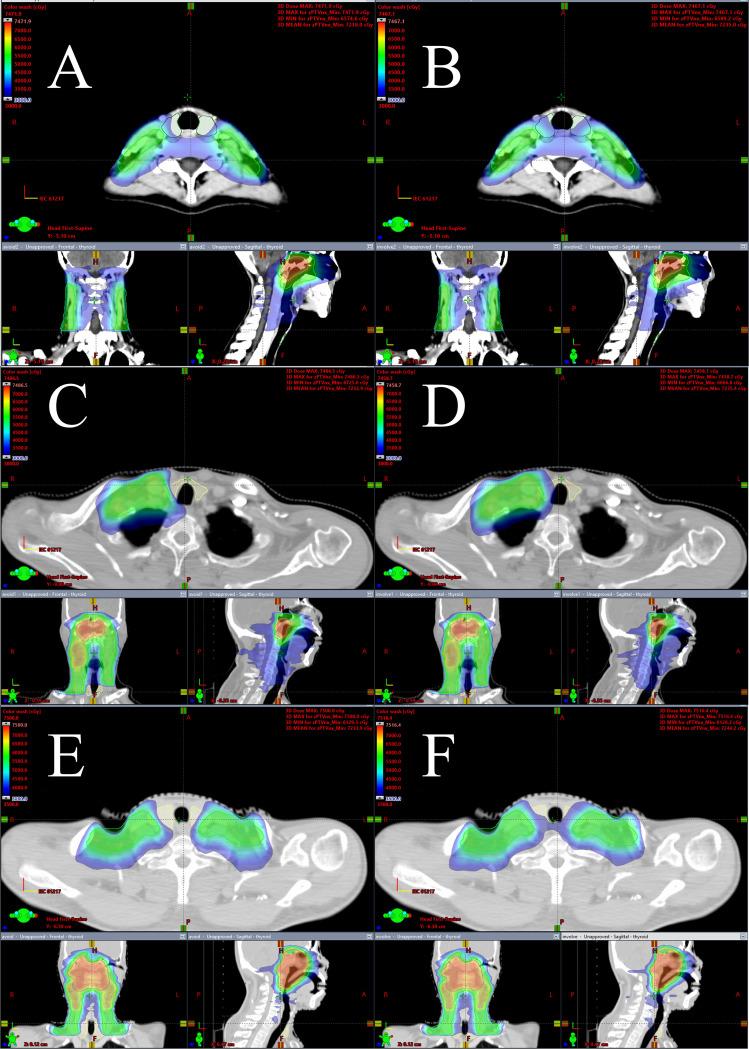

To assess the dosimetric feasibility of thyroid-sparing volume-modulated arc therapy (TS VMAT) in patients with non-distant metastatic nasopharyngeal carcinoma.

METHODS

TS VMAT plans and non-thyroid-sparing volume-modulated arc therapy (NTS VMAT) plans were created using inverse-planning VMAT and computed tomography datasets of 60 patients from two centers using the Eclipse version 15.6 treatment planning system. These patients were split up into three groups, each consisting of ten patients: the bilateral upper neck irradiation group, the one-side lower neck irradiation group, and the bilateral lower neck irradiation group. Dose volume histograms, the homogeneity index (HI), conformity index (CI), and irradiation doses to the thyroid and other OARs were used to assess the two treatment plans.

RESULTS

There were no statistically significant differences in HI, CI, and dosage distribution to OARs between the two plans, except for the bilateral lower neck irradiation group, where mild but clinically acceptable differences were observed. Surprisingly, the TS VMAT plans significantly reduced the radiation dose to the thyroid gland across all three groups without compromising target coverage, conformity, or dose homogeneity. Specifically, the mean dose to the thyroid was substantially lower in the TS VMAT plans compared to the NTS VMAT plans. Additionally, the volume of the thyroid irradiated with 40 Gy or more was also significantly reduced in the TS VMAT plans.

CONCLUSIONS

The TS VMAT plan is appropriate for radiotherapy planning in patients with non-distant metastatic nasopharyngeal carcinoma. The TS VMAT plan reduces radiation dosage to the thyroid gland compared to the NTS VMAT plan, lowering the risk of hypothyroidism without exacerbating the HI, CI, and the irradiation doses to OARs.